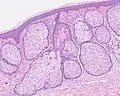

Sebaceous hyperplasia shares histopathological similarities with the typical architecture of the folliculosebaceous unit, but with larger and expanded sebaceous glands.[12][13]

H&E staining of biopsied lesion of sebaceous hyperplasia: Note the multiple, mature sebaceous lobules attached to the central dilated duct in the upper dermis. -